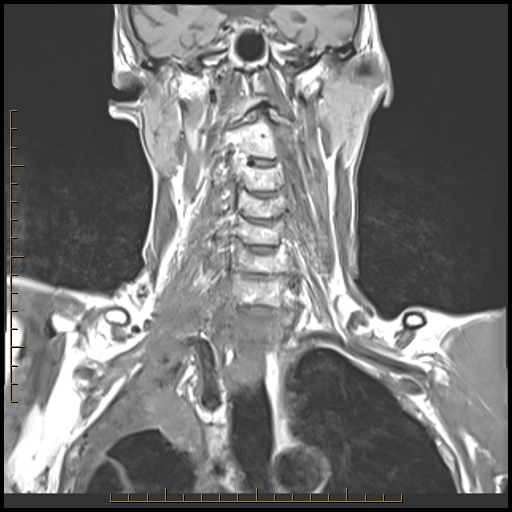

The arrows point to what primary tumor in this 77-year-old male with lung cancer? What’s invaded? Is it cleanly resectable? Come up with your own answers, then check below the images to see my findings.

A Pancoast tumor (arrow) which crosses the cupola (fat pad at lung apex) of the lung, invades the brachial plexus and the vertebra. It is NOT resectable.

ProScan Pearl: Check the lung apex on every cervical spine MRI.